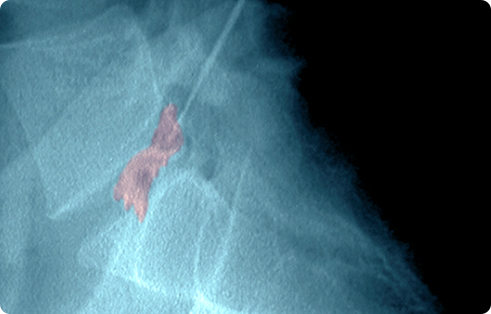

경피적 척추체 성형술

척추뼈가 부러지거나 주저앉은 경우, 척추를 바로 세우기 위한 치료법 입니다.

골절된 척추뼈가 제 기능을 할 수 있도록 긴 바늘을 통해 뼈시멘트를 주입합니다. 골절된 척추는 안정성을 되찾게 되고 척추체의 높이가 증가되어 빠른 통증 감소를 보이게 됩니다.

골다공증으로 약해진 척추뼈가 주저 앉으면 너무 아파서 꼼짝업이 누워 있거나 침술 등의 민간치료를 하는 경우가 많은데 이럴 경우 뼈가 더욱 약해지고 심지어 욕창이너 폐렴 등의 합병증으로 목숨을 잃을 수 있습니다.

경피적 척추체 성형술은 골다공증성 압박골절, 종양에 의한 골절 등의 환자에게 뼈의 안정성을 높여주고 통증을 감소시키기 위하여 주로 실시합니다.